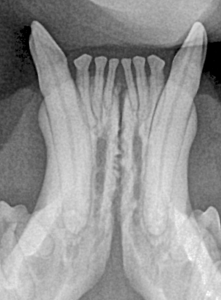

Feline Full Mouth Radiograph example